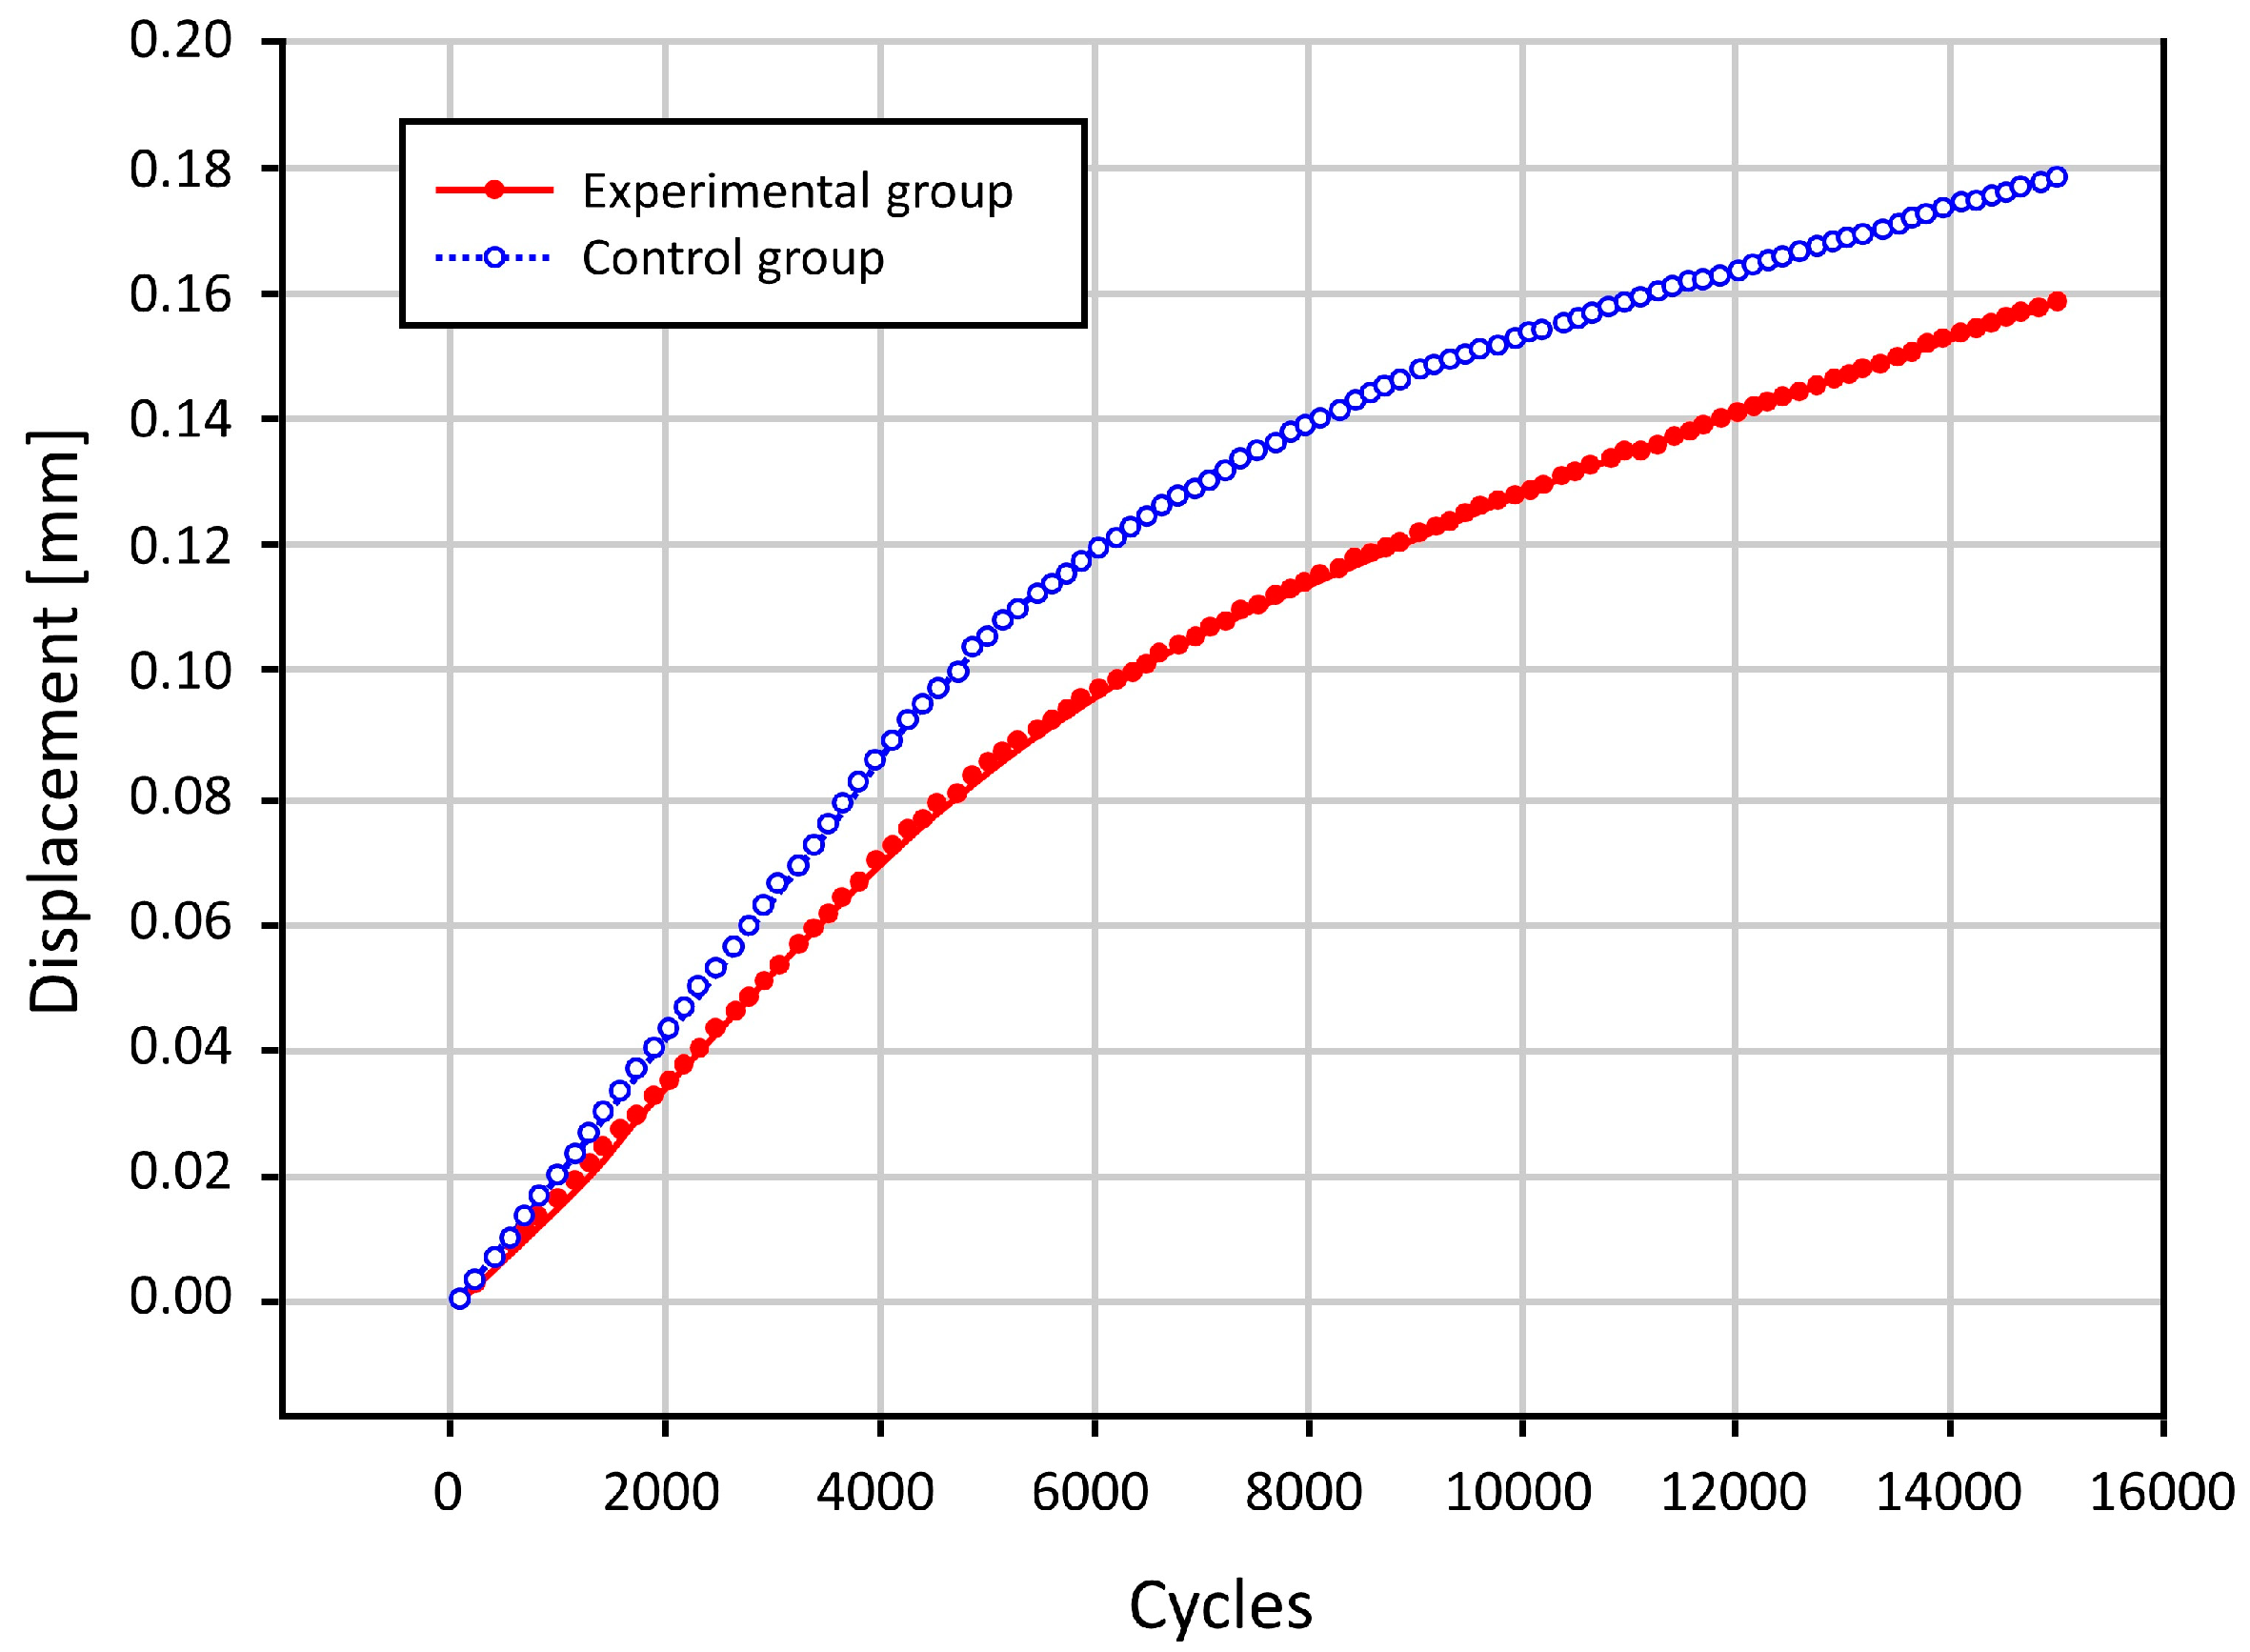

3.2. Results of the Biomechanical Study

3.3. The Bond Strength at the Bone–Cement Interface